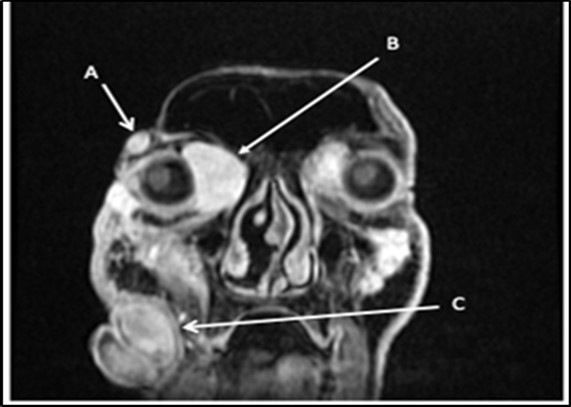

With the previous biopsy done 5 months ago, the primary working impression is neurofibromatosis. These types of lesions tend to be painless, slowly growing, solitary, skin-colored, soft, flaccid, rubbery to firm papules or nodules with a smooth surface measuring up to 2 cm. Classic characteristics include a “bag-of-worms” consistency and eyelid involvement producing an S-shaped deformity in cases of the plexiform variants1. The lesion also invaginates with pressure. The prevailing diagnostic criteria of Figure 2. Multiple facial lesions are radiologically consistent with neurofibromas. (A) 1.8x0.9x1.7cm right lateral temporal mass (B) 3.2x3.3x4.5cm right medial intraorbital mass (C) 8.6x7.3x6.0cm right nasal mass neurofibromatosis type 1 are met if 2 or more of the following are present: (1) ≥ 6 café au lait patches (2) ≥ 2 neurofibromas of any type, or 1 plexiform neurofibroma (3) axillary or inguinal freckling (4) ≥ 2 lisch nodules, (5) optic glioma, (6) sphenoid dysplasia or thinning of long bone cortex with or without pseudoarthrosis (7) first-degree relative diagnosed with neurofibromatosis type12. In contrast to this, our patient did not satisfy any clinical manifestations of Neurofibromatosis type 1. The closest differential of neurofibroma would be a schwannoma. If present on the orbit, they are insidious and proptose gradually without pulsations. Most tumors infiltrate the superior quadrant, causing inferiorly displaced proptosis or frank hypoglobus3. Patients may experience diplopia, eye movement limitation, diminished visual acuity, and optic nerve compression symptoms, including scotomas dyschromatopsia, and impaired contrast sensitivity. They may also experience pain or paresthesia in the distribution of the nerve. In severe cases, there may be a palpable orbital mass4. Only one case has been reported of a bilateral orbit involvement5. Another differential would be the malignant transformation of neurofibroma. Malignant peripheral nerve sheath tumor may arise from a preexisting nerve sheath tumor in neurofibromatosis type 1 and can arise in virtually any anatomic location. The most common sites are the trunk and extremities, followed by the head and neck. There is no gender preference, and it tends to occur in younger individuals with Neurofibromatosis1. Histologic evaluation is necessary but not always specific and requires correlation with clinical and radiologic findings6. At this point, the clinical presentation is consistent with the previous histopathologic diagnoses, that of a neurofibroma. Although a neurofibrosarcoma would also have a similar presentation at its early stages, its predilection for arising from NF type 1 lesions is not seen in our patient.

Figure 2.Multiple facial lesions radiologically consistent with neurofibromas. (A) 1.8X0.9X1.7cm right lateral temporal mass (B) 3.2X3X4.5 cmright medial intraorbital mass (B) (C) 8.6X7.3X6.0 cmr right nasal mass